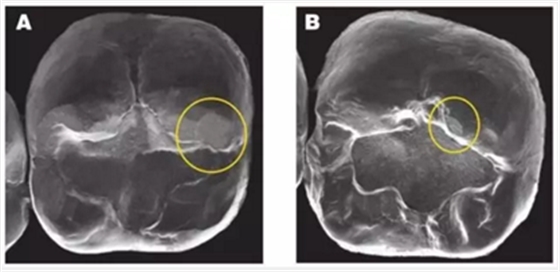

3. 對(duì)頜牙對(duì)牙冠的磨損:令人吃驚的是,各種類型的對(duì)頜牙(釉質(zhì)、鑄造金屬、復(fù)合樹(shù)脂還是瓷)都會(huì)對(duì)牙冠造成磨損平面。磨損程度最高的是瓷,其次是釉質(zhì)。鑄造金屬和復(fù)合樹(shù)脂也會(huì)造成磨損平面(見(jiàn)下圖)

圖像A顯示了對(duì)頜牙在BruxZir全鋯冠上造成的磨損的平面,黃色圓圈代表復(fù)合樹(shù)脂和釉質(zhì),橙色圓圈代表瓷。圖像B顯示了對(duì)頜牙為鑄造金屬修復(fù)體時(shí),對(duì)切削類e.maxCAD單冠造成的磨損平面。兩種牙冠表面都有小的磨損平面,而且他們的對(duì)頜牙都顯示出了良好的結(jié)果。臨床上,對(duì)頜牙的每種材料(瓷、樹(shù)脂、釉質(zhì)、鑄造金屬)被磨損的程度幾乎是等同的。